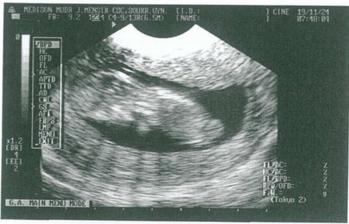

11.12.2008 druhá poradna. Vsechno je v nejlepsim poradku - prcek byl krasne videt ze vsech stran :o) nadherny pohled....nemohla jsem se vynadivat. 19.12. nas ceka NT screening.

19.12.2008 návštěva Gennetu. Vše dopadlo na výbornou a krásně jsme viděli mrňouska jak se mu dobře daří. Navíc jsme krásně slyšeli jeho srdíčko :o) no prostě byly jen krásné dojmy spojené s předvánočním časem.....